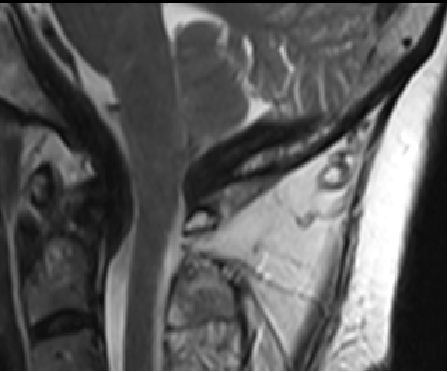

2013-5-16 MRI

2013-5-16